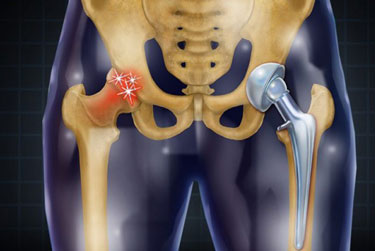

Dr Prateek Kumar is a highly qualified compassionate orthopaedic surgeon with over 15yrs of experience in field of Orthopaedic & Arthroplasty.He has received his medical education from renowned Institutions in India & has continuously updated his knowledge to stay at the forefront of medical advancement. Dr.Prateek Kumar is committed to providing the best possible care to his patients ensuring their comfort and well being throughout their treatment.